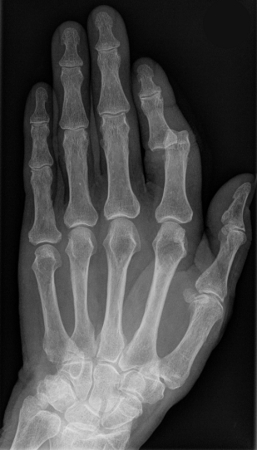

X-ray showing dislocation of the proximal interphalangeal joint, left index finger

Hellerhoff, CC BY-SA 3.0 via Wikimedia Commons